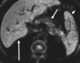

Focal iron deposition